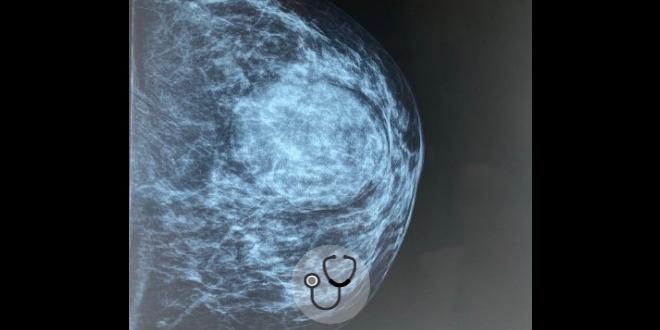

Mulher branca, 39 anos, nuligesta, sem comorbidades, vem à consulta de ginecologia bastante ansiosa por apresentar “caroço” na mama esquerda.

A ressonância magnética (RM) das mamas vem sendo estudada como método complementar para detecção do câncer de mama em mulheres com alto risco – mamas densas